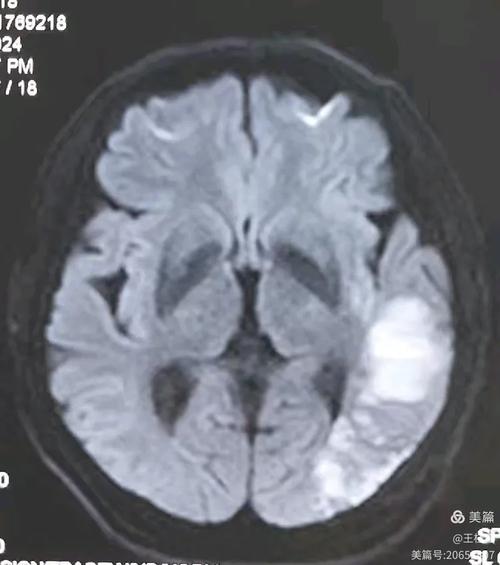

(图片来源网络,侵删)

急性期治疗(在医院进行)

- 时间就是大脑:一旦怀疑脑梗,需要立即就医,在“黄金时间窗”(通常是发病后4.5小时内)内评估是否可以进行静脉溶栓治疗,或者对于符合条件的患者进行动脉取栓,即使是小面积梗塞,如果时间窗合适,溶栓也可能有益。